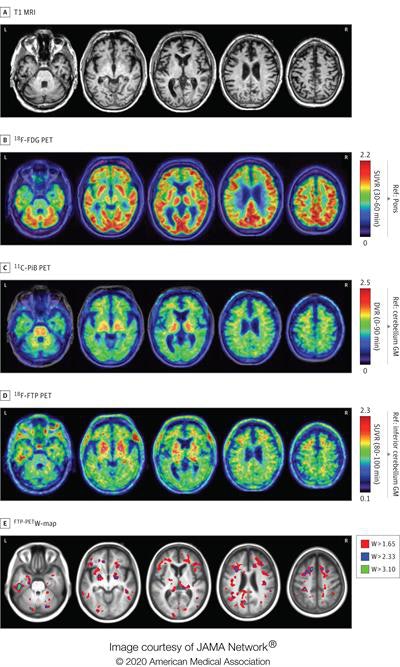

T1-weighted MR images (top row) demonstrate mild medial temporal and frontal atrophy. FDG-PET images (second row) show mild hypometabolism in the medial temporal, medial and dorsolateral frontal, and peri-insular regions, while the PiB-PET images (third row) were visually rated as negative for cortical retention. Flortaucipir-PET (fourth row) shows widespread patchy binding predominantly in the left greater than right frontotemporal areas. The flortaucipir-PET maps (bottom row) show that these focal increases are higher than what would be expected considering the patient's age. DVR: distribution volume ratio, GM: gray matter, Ref: reference region, and SUVR: standardized uptake value ratio with acquisition windows in parentheses. Images courtesy of JAMA Neurology and Mantyh et al.

Some four years before his death, he underwent an MRI scan, a PET exam with carbon 11-labeled Pittsburgh compound B (PiB), and a PET scan with flortaucipir. The results were later evaluated for abnormalities by readers who were blinded to the subject's autopsy data.

The flortaucipir-PET images showed radiotracer uptake spread about in a "patchy, frontotemporal-predominant pattern" that coincided with regions of neurodegeneration on MRI and hypometabolism on FDG-PET. Pathological results also confirmed the subject had stage IV CTE.